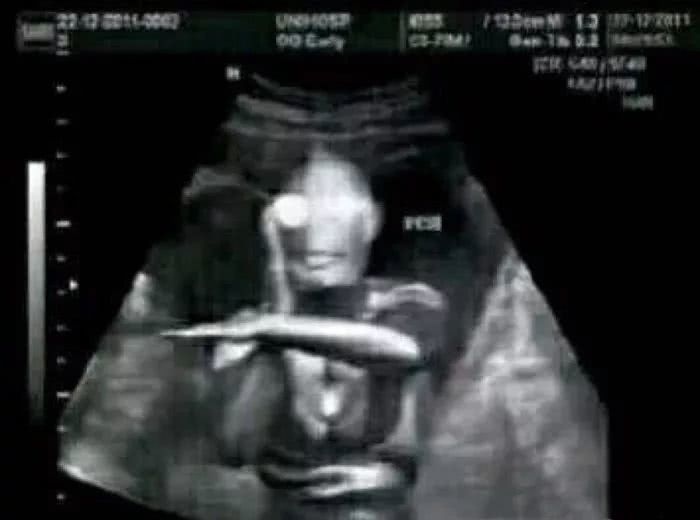

一位网友共享了自己的阅历,她是在恶作剧中发现的。她在微博上看到了一个奥特曼的b超图,所以用它骗老公和闺蜜说自己怀孕了。